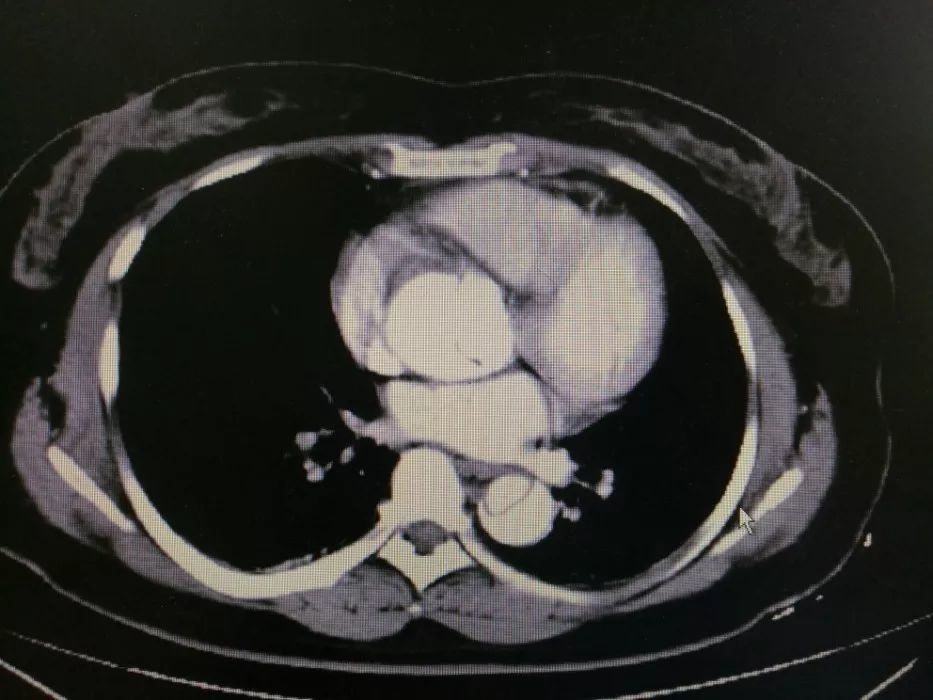

增强CT的副作用是几天 参与医生 福建省中医药大学附属康复医院林增如副主任医师 CT检查又分为CT平扫和CT增强。CT增强是通过一种增强剂,又称为碘剂,打入血管,通过血